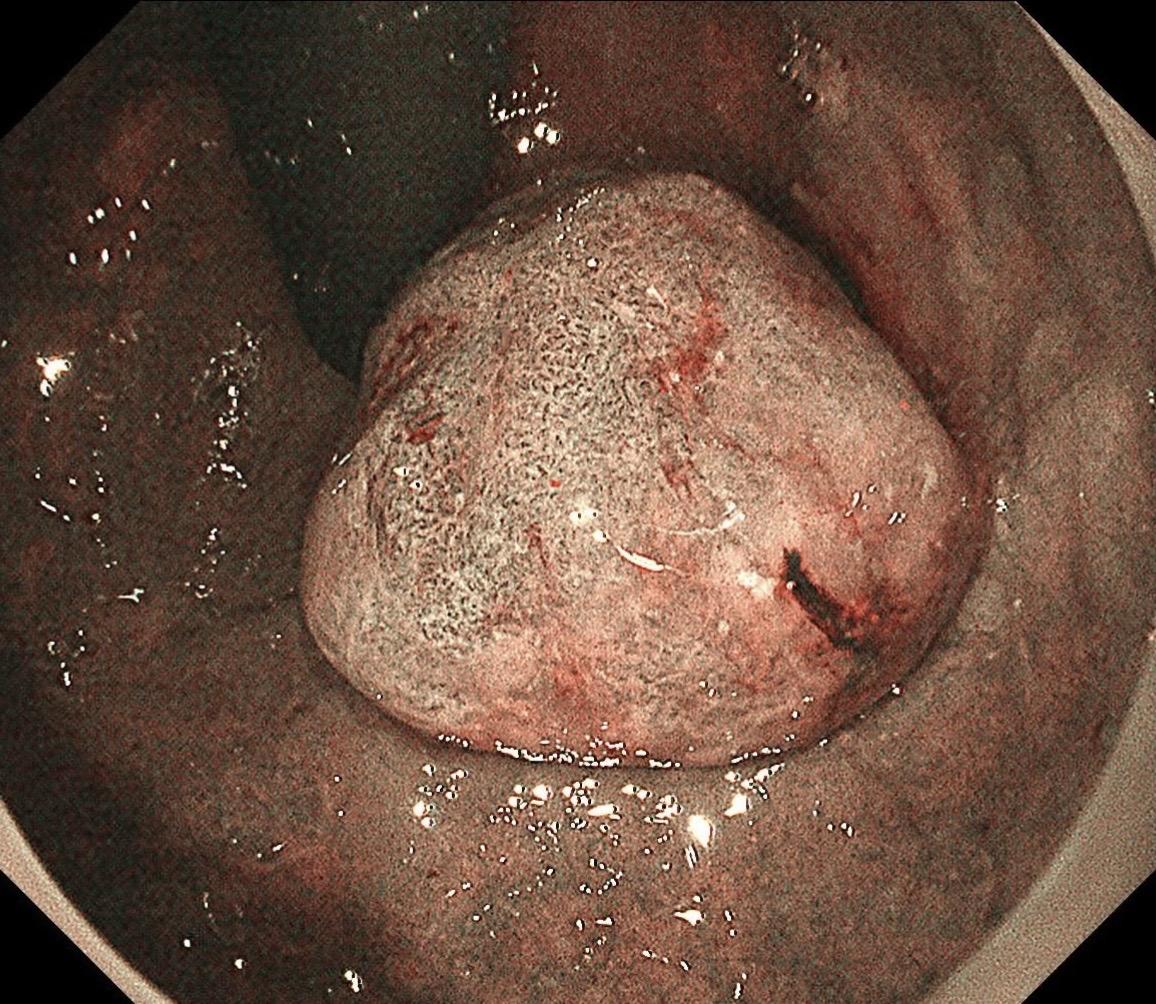

低位早期直肠Ca.男,37岁,大便带血1月,距齿状线2cm,ESD切除,还好来得及时~